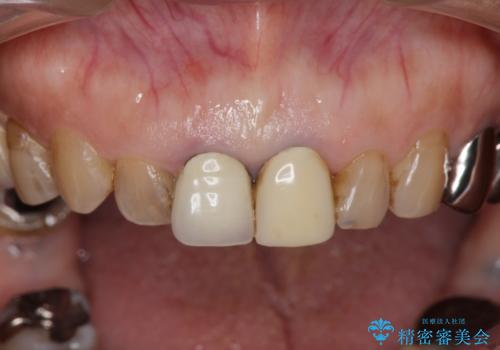

前歯の審美改善

- 孫娘の結婚式に合わせて前歯を綺麗にして写真映りをよくしたいと来院されました。

結婚式に合わせて根管治療からのやりかえを短期集中治療で計4回で終える計画を立てます。

- 40万円(仮歯・ファイバーコア・ジルコニアクラウン×3)費用は治療当時の料金となります